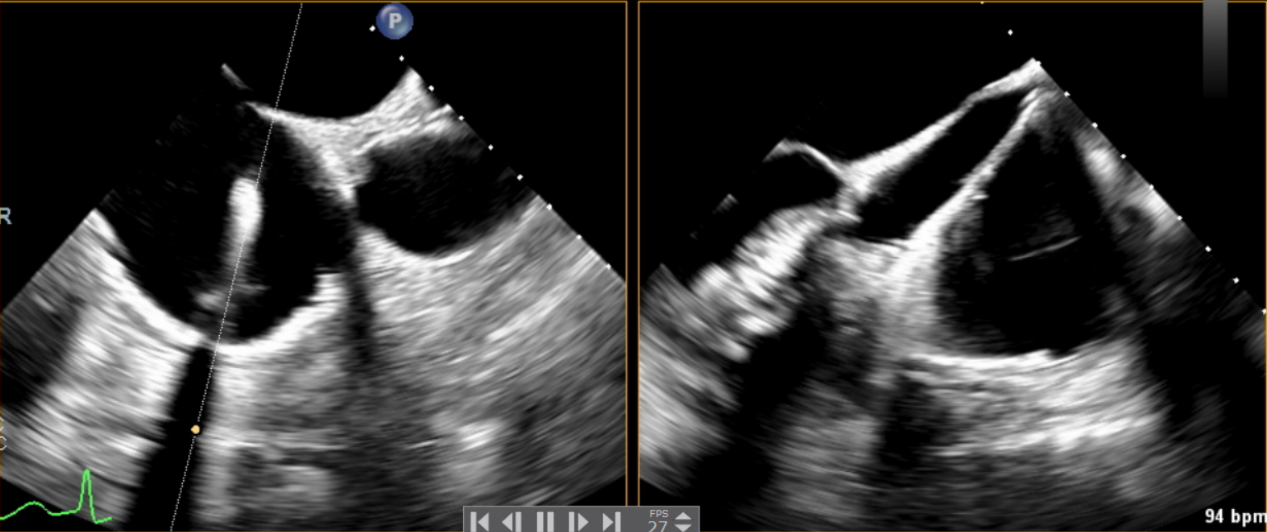

術中輸送器在超聲引導下調整位置